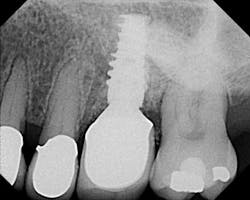

- Taking an X-ray to establish baseline bone level.

- Take an annual X-ray; compare bone height from the baseline radiograph.